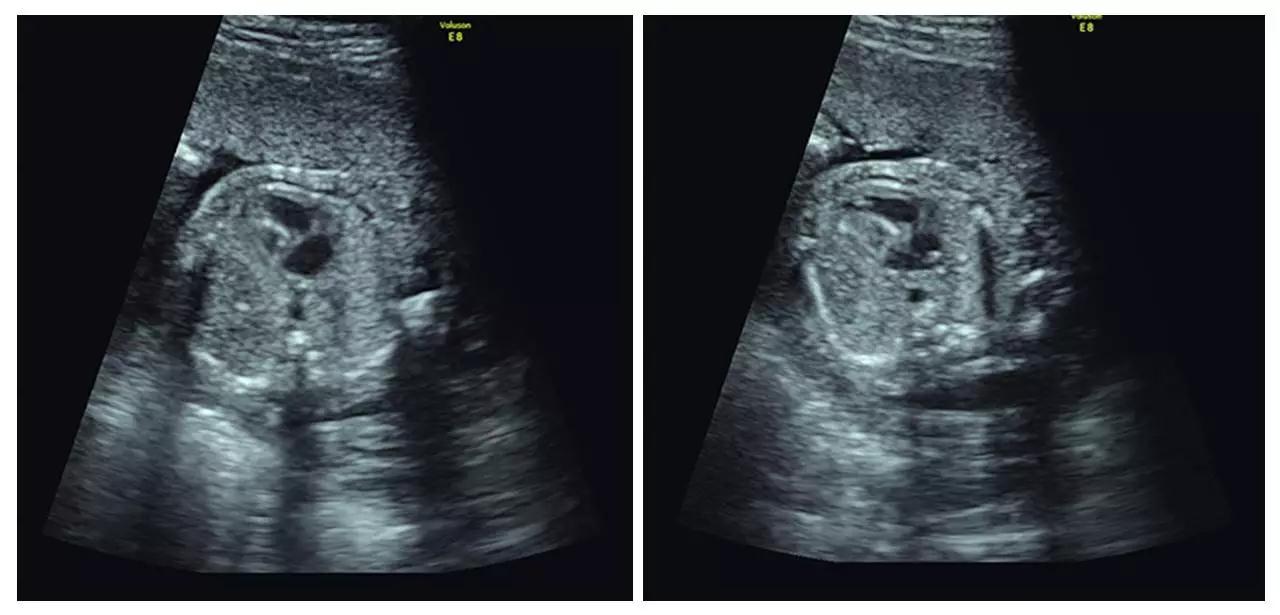

(左心发育不良)

(胸腹腔积液、全身水肿)

(颈后水囊瘤)